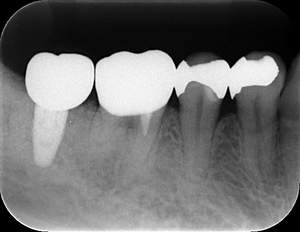

インプラント治療の症例1

レントゲン写真

- 透過像

| 年齢 | 50代・男性 |

|---|---|

| 主訴 | 右下歯が疼く |

| 治療内容 | ・右下6番インプラント ※1:FGG(遊離歯肉移植術)とは、足りない歯ぐきを上顎から上皮を切り取り移植する外科手術 |

| 治療費 | 合計:902,000円(税込) ■内訳 |

| 治療期間 | 9ヵ月 |

| 治療方針 | 右下の当該歯は歯根破折により保存不可能と診断しました。歯周疾患も伴っていたため抜歯後に骨吸収※1が大きく起こることが予測できました。チタンメッシュ併用骨再生誘導法(GBR※2)を選択しインプラント埋入と同時に行い自然な歯槽骨のラインを再現しました。またGBRを行う際にインプラント辺縁の付着歯肉の減少が起こる為、遊離歯肉移植術(FGG※3)を行い清掃性を考慮した形態に仕上げました。 ■治療方針の解説 治療した右下の歯をレントゲンで撮影したところ根本の部分に黒く写る箇所があり「根尖性慢性周囲炎※1」と診断。また歯周病も進行していました。 ※1 骨吸収・・・歯槽骨という歯を支える骨がなくなっていくこと |

| 担当者所見 | 主訴の右下だけでなく歯茎の腫れ、発赤があり不良補綴や不良充填など他にも治療箇所が多数ありました。プラークコントロールが不良であった為まずはブラッシング指導を行いセルフケアの重要性を理解していただくところからスタートしました。 右下6番の歯はインプラント治療を行なった結果審美的にも機能的にも患者様の満足を得ることができました。骨造成と歯肉移植も行なった為インプラントを支える十分な歯周組織の獲得ができたと思っております。 |